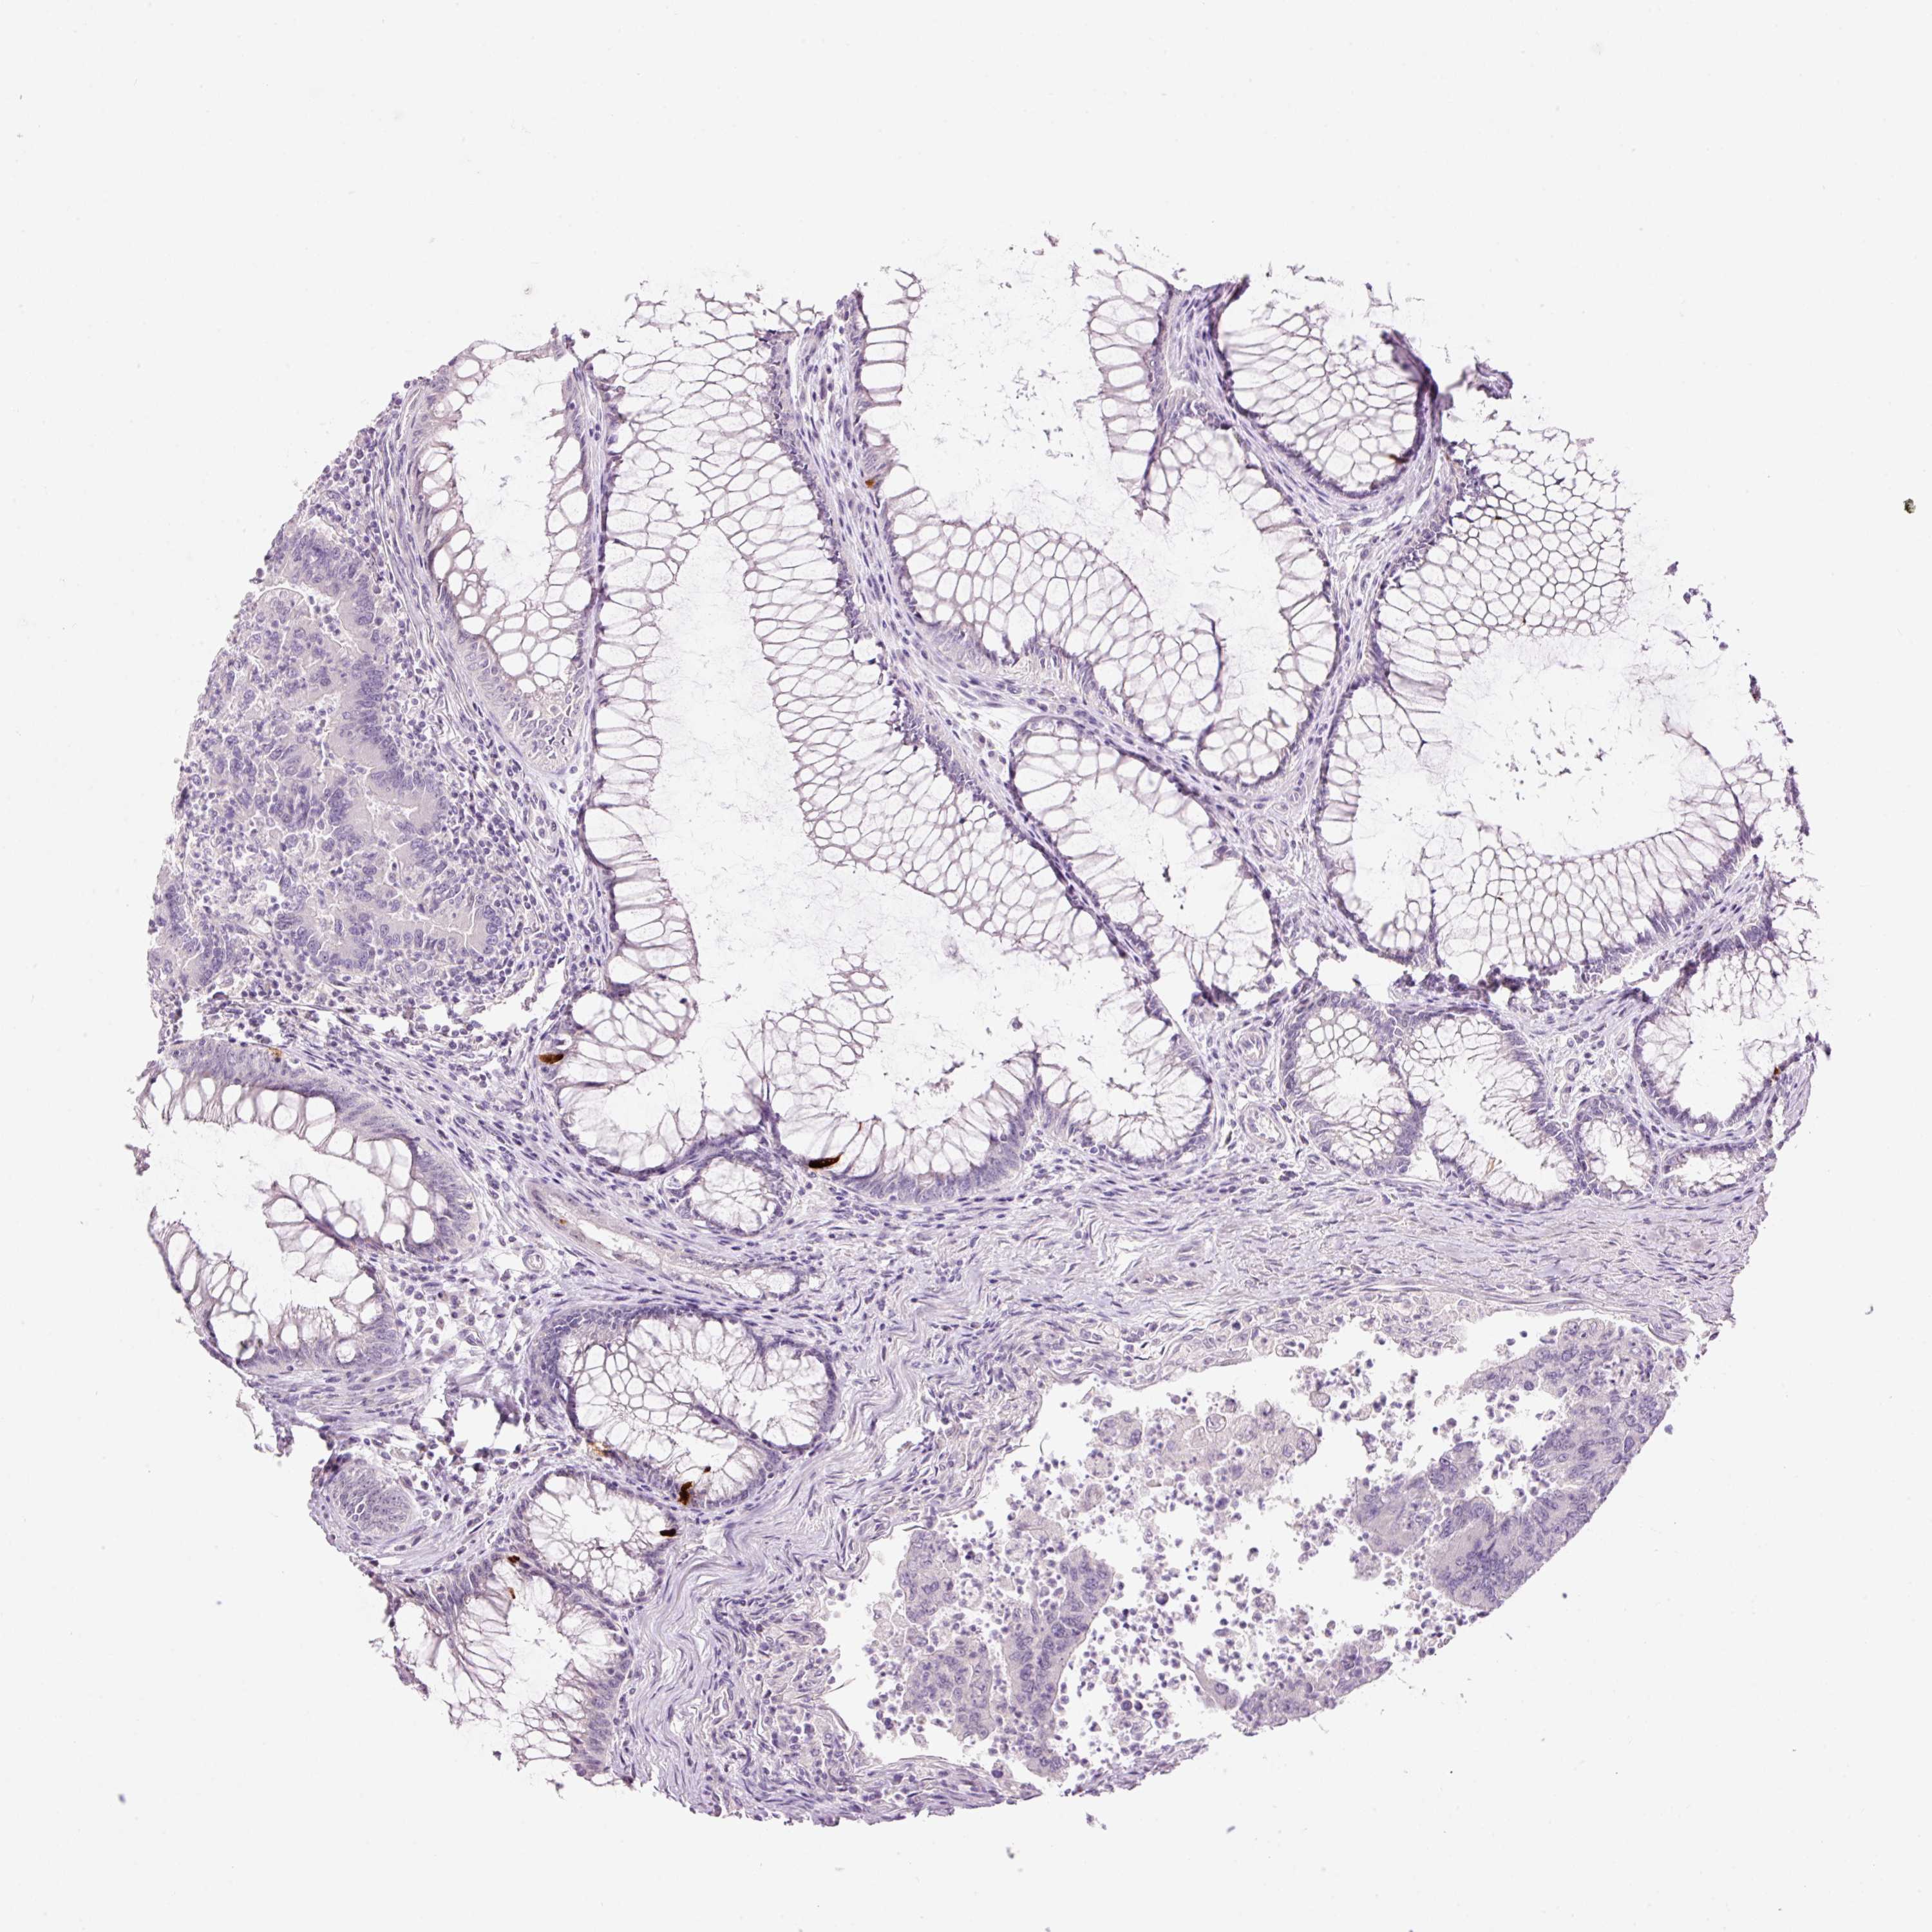

Colorectal cancer

Human cancer

Colon adenocarcinoma